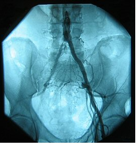

Below you can see the sequestered fragment in my own back; it has migrated cephalad, or towards the head, from the L3/L4 disc. Read more at femoral nerve damage.

Classically the L4 nerve root is pinched by the L3/L4 disc, though the L3 root can be affected by a lateral herniation into the IVF.